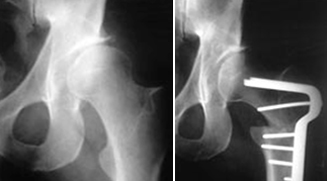

Em algumas ancas displásicas há uma cabeça aplanada e com um volumoso osteófito medial (capital drop) e a osteotomia de valgização pode aumentar a congruência articular, a medialização do centro de rotação, aumentar o comprimento do membro, melhorar a função dos abdutores pelo melhor posicionamento do grande trocanter.

Quando houver sintomatologia (dor, claudicação) e alterações imagiológicas há indicação para cirurgia, para correção do valgo e para melhorar a congruência articular, diminuindo a sintomatologia e melhorando o bem-estar e qualidade de vida do paciente, e prevenindo a evolução e instalação da artrose grave.

A cirurgia deverá ser feita antes que haja artrose avançada.